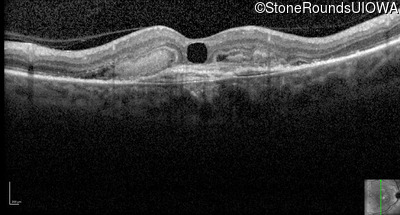

Optical Coherence Tomography - Right - 20/80 +1

Exemplar / OCT Stack